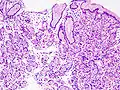

- Микроструктура полипов желудка

Полип фундальных желёз